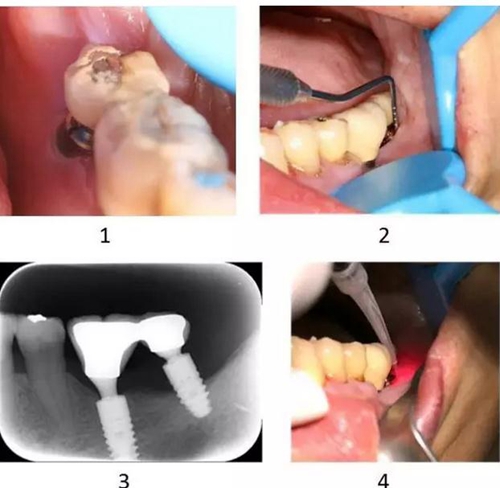

圖2-5-7 半導(dǎo)體激光輔助37種植體周圍炎的非手術(shù)治療

1~3. 種植體周圍軟組織炎癥,牙齦退縮,附著喪失,伴明顯骨吸收 4. 810nm 半導(dǎo)體激光,1W,間斷發(fā)射模式袋內(nèi)照射,明顯緩解患者種植體周圍炎引起的軟組織不適、疼痛,且療效持續(xù)